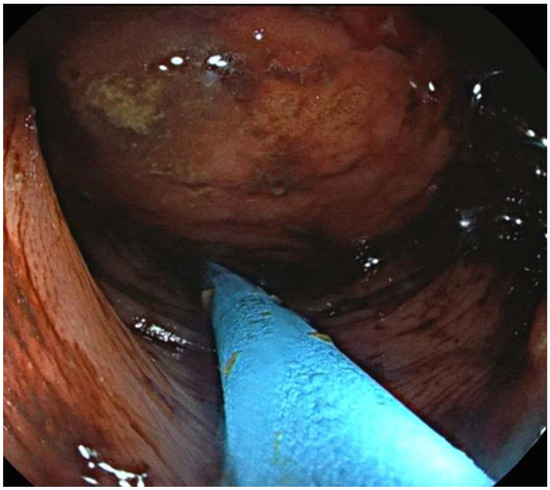

2.4. Endoscopic Techniques

- 7 cases in which the lipoma was presumably associated with symptoms including abdominal pain, hematochezia, and even intussusception. In 3 of these cases, we had a pre-treatment diagnosis as the symptoms required the execution of pre-endoscopic radiological examinations.

- 8 cases in which the discovery and subsequent removal of the lipoma seem to be accidental, made during routine check-ups or follow-ups (obviously without warning symptoms).